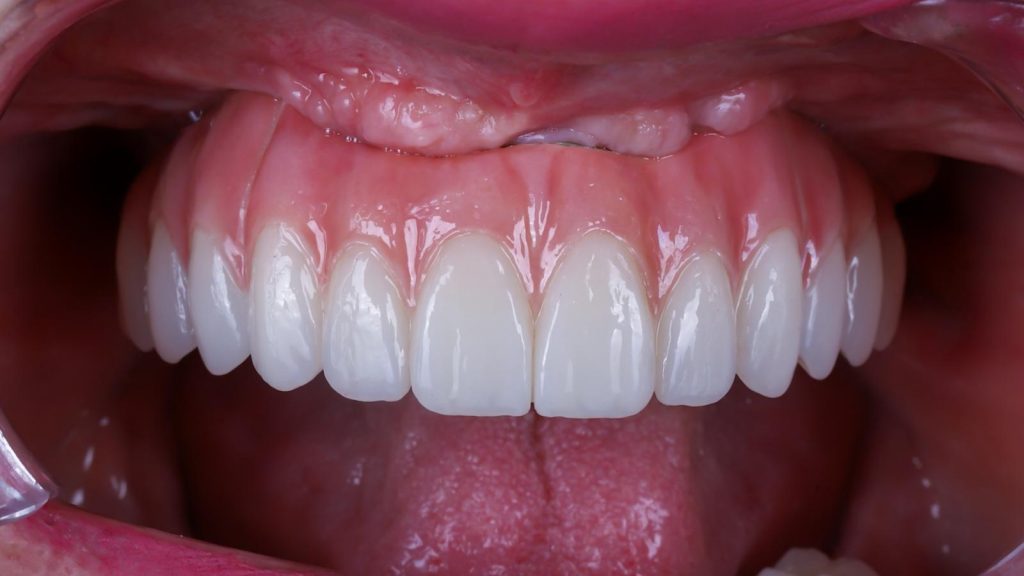

Visualizar la transformación

Los cambios de imagen de la sonrisa favorecen mejoras cuidadosas y matizadas, para obtener resultados naturales que garanticen el equilibrio general y la armonía facial.